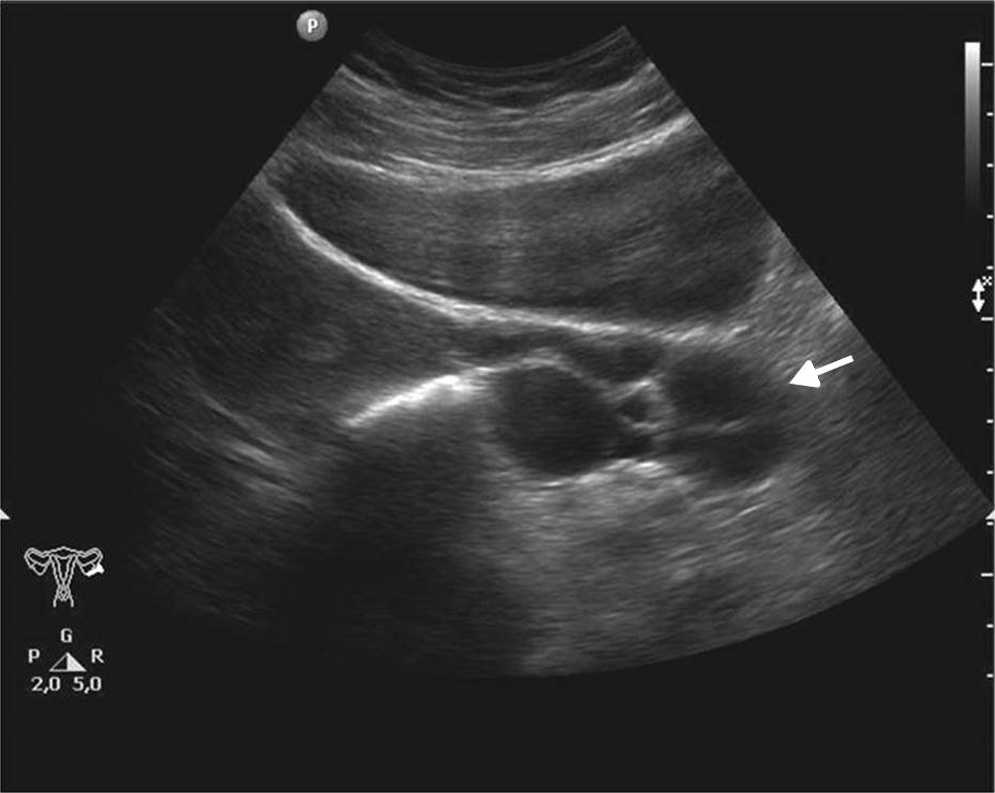

Las principales causas de esta dolencia son los quistes de ovario simples o hemorr??gicos, los embarazos ect??picos, las enfermedades inflamatorias pelvianas, las torsiones de ovario y otras patolog??as, muchas de las cuales tienen caracter??sticas ecogr??ficas propias que permiten su diagn??stico5 (figs. 1-3).

La ecograf??a determina la naturaleza s??lida o qu??stica de las masas anexiales, la presencia de septos o elementos s??lidos, y su vascularizaci??n con la exploraci??n Doppler (fig. 4). Estos hallazgos ayudan a determinar la benignidad o malignidad de la masa5,10.